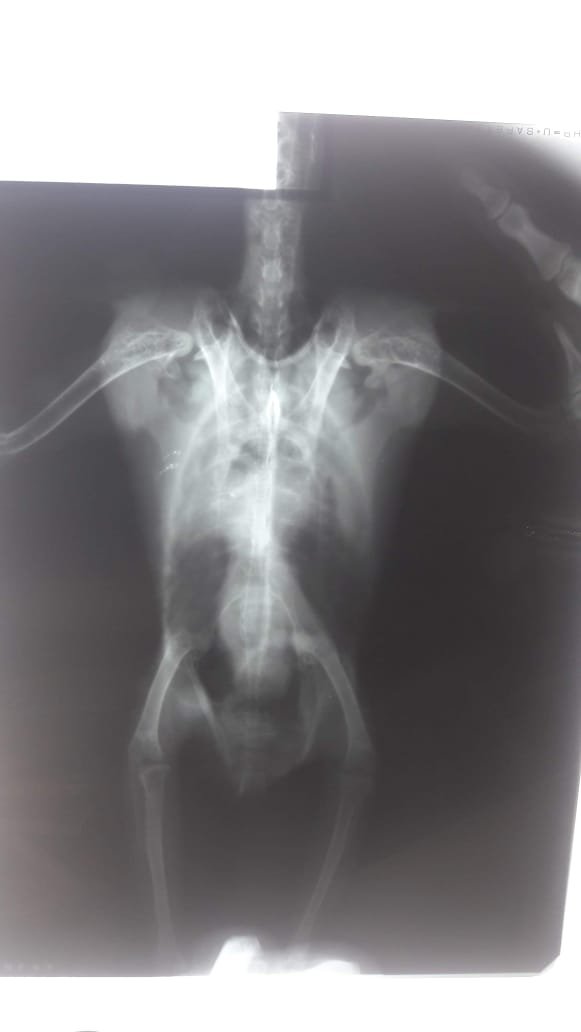

13. Здравствуйте мне нужна помощь в лечении жако Кузи. Неделю назад попугай перестал кушать, пить, петь, стал не активен. Посадили под лампу дали сорбент предполагая отравление. На след день вторник 29 сентября повезли в клинику сделали рентген, взяли анализы: мазок из зоба, помет, общий крови. Диагноз инфекция верхних дыхательных путей, аспергилез. Выписали лечение ниже выложу все фото которые есть. Вечером начали курс лечения давали антибиотик цефалексин, нестыден, трихопол, давала, все это мешали с кашей для птенцов нутриберд в 20 куб шприце и выпаивали 2 р в день утром и вечером, но улучшений небыли. В субботу вечером добавили вориконазол и укрыли, в воскресение утром после дачи лекарства спустя 40 20 мин началась рвота. Птица похудел, сам ест очень мало несколько семечек в день, несколько гранул, один укус фрукта, вялый не активный сидит под лампой все время. Сегодня утром тоже вырвал после дачи лекарства с кашей. Ест совершенно без аппетита, кашу с лекарствами всунуть проблема, зоб перед едой совершенно пуст. Помогите я не знаю, что делать, врача у нас нет ниже кину ссылку на пост почему нет врача. Подскажите как его кормить? Сколько раз в день? Какие дозы каши? Неделю сама не могу не есть не спать, скоро с ума сойду… простите за сумбур… Ps. Извините если что то не так с фотографиями, я незрячая и комп некоторые вещи плохо озвучивает. С попугаем помогает муж. Если есть возможность мне удобнее пересылать фото и видео по вотсап и телеграмм. вот история почему нет врача. у знакомых птичников спрашивала, говорят им от вориконазола лучше, птицы оживают на второй третий день. а уменя кузюня угасает. с каждым часом все хуже.